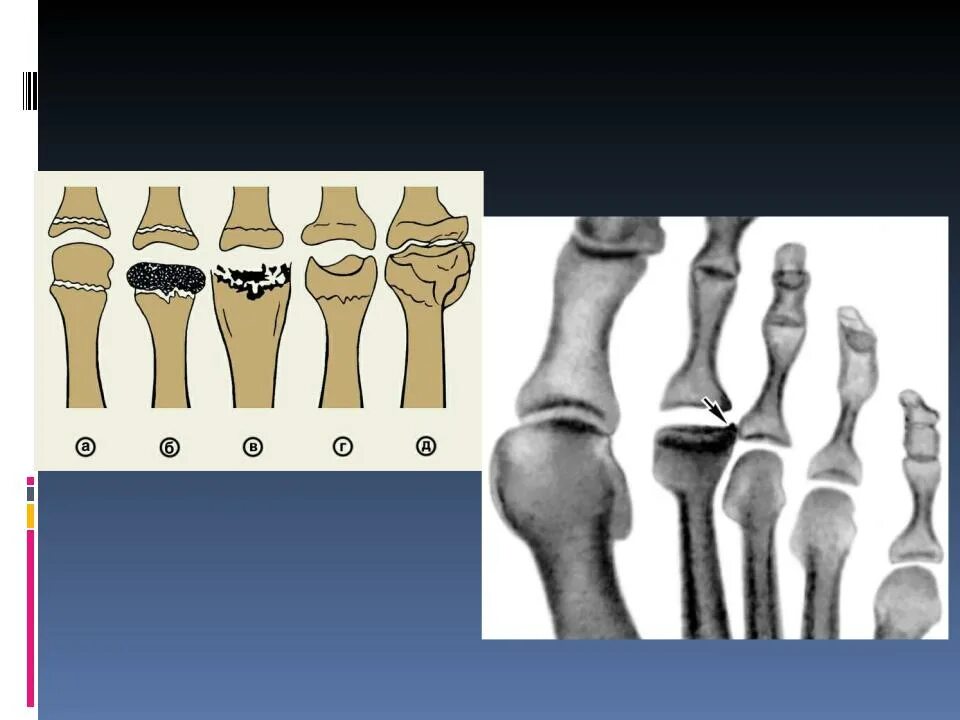

Келлера 3